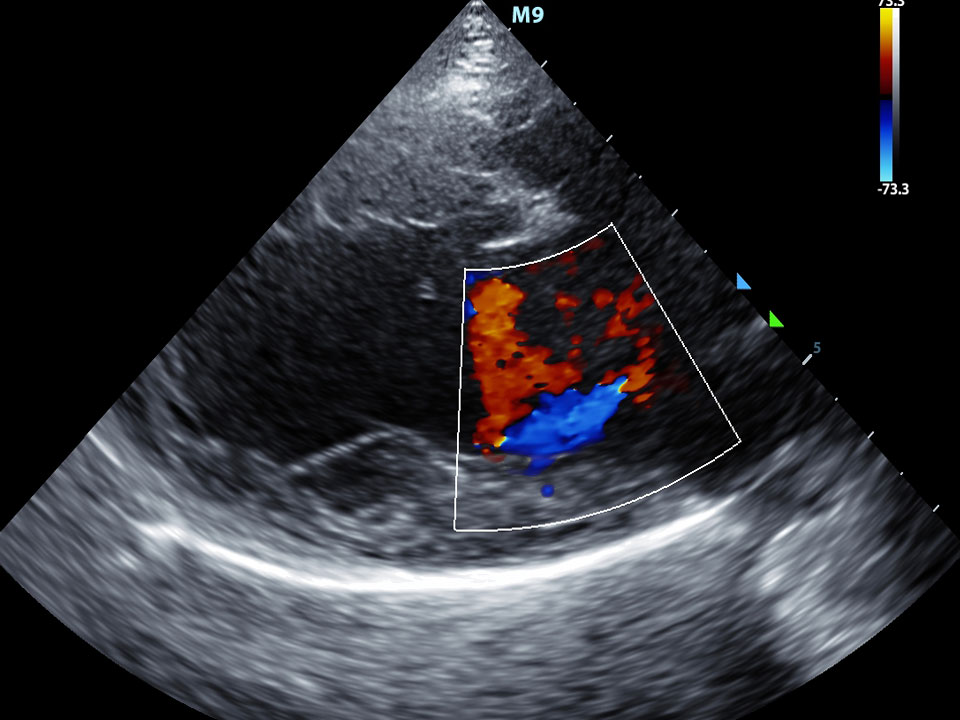

Bij een Ventrikel Septum Defect (VSD) zit er een opening tussen de linker- en het rechterkamer, onderin het hart. Het hart ligt in de borstholte tussen de 2 longen in. Het ligt iets meer aan de linkerkant van het borstbeen. Het hart van een volwassene is ongeveer 2 vuisten groot en weegt ongeveer 300 gram.. Extra volume belast namelijk het hart. De rechterkant van het hart moet harder werken en wordt hierdoor groter. Een atriumseptumdefect veroorzaakt meestal niet meteen klachten; het kan daardoor vele jaren duren voor het gaatje wordt ontdekt. Een ASD leidt meestal tot klachten: kortademigheid; hartritmestoornissen (op jongvolwassen leeftijd);